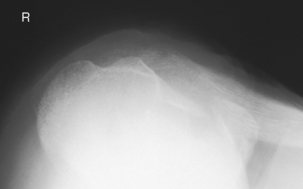

Scapular Y lateral—anterior oblique position and Neer method (S)

Scapular Y lateral and Neer method critique